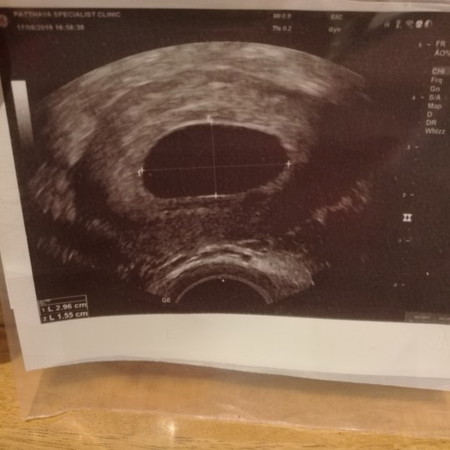

8wแล้วยังไม่เจอน้องเลยกลัวเป็นท้องลม

ปกติ 8 วีค เจอตัวแล้วนะคะ แต่รออีกสัก 2 อาทิตย์ค่อยไปซาวน์ใหม่ หรือลองไปตรวจที่ รพ.อื่นหรือคลินิกอื่นลองดูนะคะ ซาวด์หน้าท้องไม่เจอก็ลองซาวด์ผ่านช่องคลอดดูค่ะ